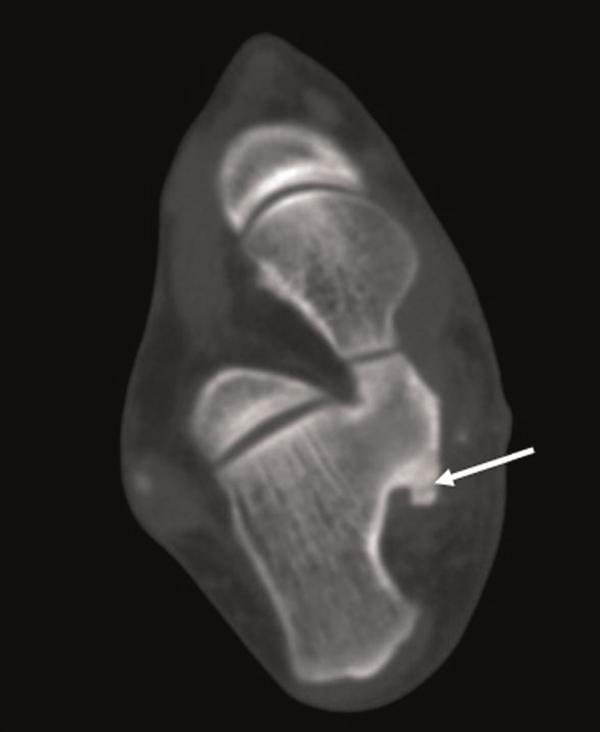

We report the clinical and radiologic findings of a calcaneal osteochondroma with an extremely rare placement and painfull, rapid reccurence following surgical excision in a skeletally mature female. The lesion showed growth the first-operation later and was re-operated. Histopathological examination did not show malignancy.

我们报告了一名骨骼成熟女性跟骨骨软骨瘤的临床和影像学表现,该肿瘤位置极其罕见,手术切除后疼痛且迅速复发。病变在首次手术后出现生长并再次接受手术。组织病理学检查未显示恶性。